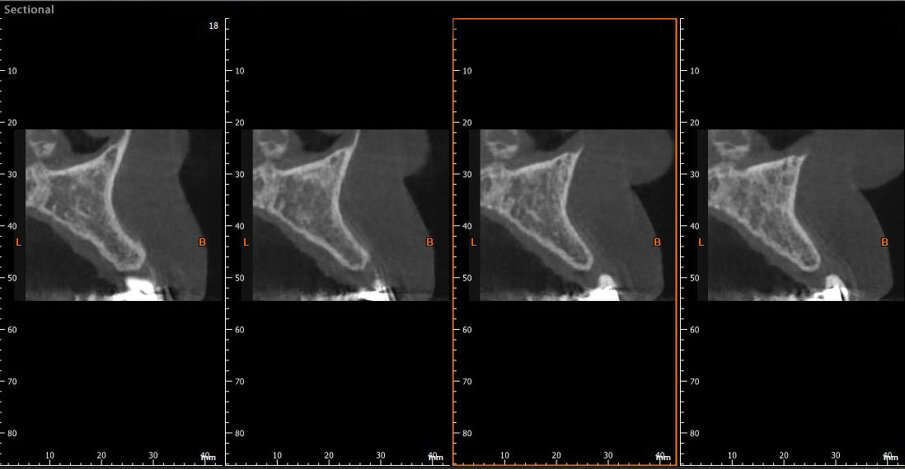

Gli esami radiografici completano l’approccio diagnostico iniziale e lo studio delle radiografie endorali del gruppo frontale, di un’ortopantomografia delle arcate dentarie e di una CBCT permettono di evidenziare un corretto allineamento radicolare degli elementi dentari contigui all’edentulia da trattare e una moderata atrofia orizzontale della cresta alveolare edentula (Fig. 1). Trattandosi di una riabilitazione del settore frontale è opportuno realizzare una dettagliata analisi estetica supportata da un esame fotografico corredato di fotografie extraorali (del volto e del sorriso), fotografie intraorali e da una ceratura diagnostica. L’attenzione iniziale è rivolta principalmente all’analisi dei tessuti molli e degli elementi dentari; in particolare, nel caso descritto, la paziente non presenta fattori estetici sfavorevoli dal momento che si riscontra la presenza di una linea del sorriso media, elementi dentari in area estetica sani e non discromici, fenotipo gengivale spesso, simmetria della festonatura gengivale e buona rappresentazione delle papille interdentali. Osservando in visione frontale la situazione clinica iniziale si evidenzia una lieve recidiva ortodontica dell’elemento 1.1 che si presenta leggermente mesializzato e vestibolarizzato rispetto alla sua posizione ideale (Fig. 2).

Fig. 1 - CBCT della situazione clinica iniziale.